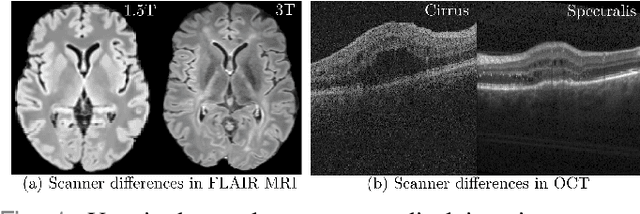

Abstract:Deep networks are now ubiquitous in large-scale multi-center imaging studies. However, the direct aggregation of images across sites is contraindicated for downstream statistical and deep learning-based image analysis due to inconsistent contrast, resolution, and noise. To this end, in the absence of paired data, variations of Cycle-consistent Generative Adversarial Networks have been used to harmonize image sets between a source and target domain. Importantly, these methods are prone to instability, contrast inversion, intractable manipulation of pathology, and steganographic mappings which limit their reliable adoption in real-world medical imaging. In this work, based on an underlying assumption that morphological shape is consistent across imaging sites, we propose a segmentation-renormalized image translation framework to reduce inter-scanner heterogeneity while preserving anatomical layout. We replace the affine transformations used in the normalization layers within generative networks with trainable scale and shift parameters conditioned on jointly learned anatomical segmentation embeddings to modulate features at every level of translation. We evaluate our methodologies against recent baselines across several imaging modalities (T1w MRI, FLAIR MRI, and OCT) on datasets with and without lesions. Segmentation-renormalization for translation GANs yields superior image harmonization as quantified by Inception distances, demonstrates improved downstream utility via post-hoc segmentation accuracy, and improved robustness to translation perturbation and self-adversarial attacks.